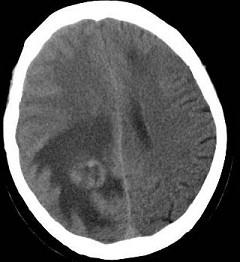

问题 男,62岁,既往有右肺腺癌史,现出现头痛、头晕、恶心、视物模糊,CT检查如图,最可能的诊断是()

选项 A.脑梗死 B.胶质瘤 C.脑膜瘤 D.畸胎瘤 E.脑转移瘤

答案 E